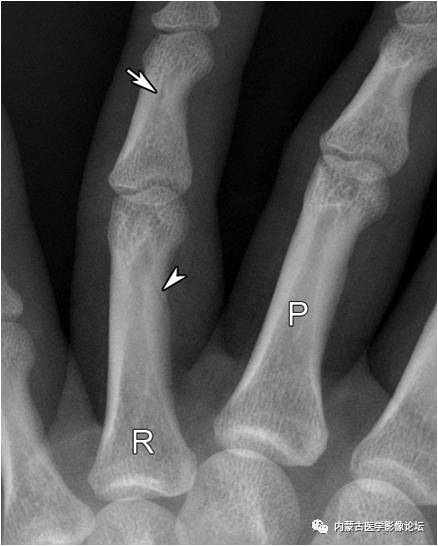

拇指籽骨:拇指指间关节籽骨(箭)较小且略呈三角形,与拇指掌指关节籽骨(箭头)不同,勿误认为撕脱骨折。